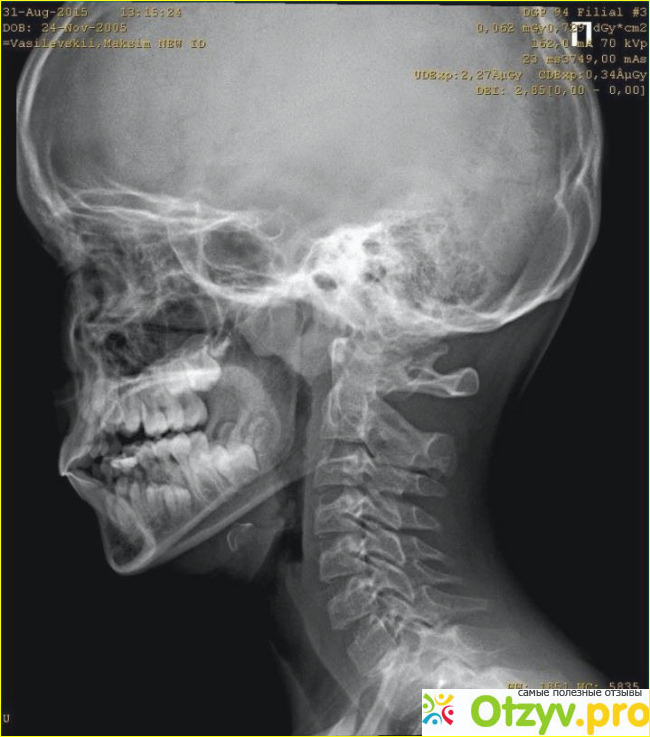

Речь идет об отростке в шейном отделе, в основном это второй позвонок, в норме он быть в форме полукольца или кольца не должен, в этом и заключается аномалия. Просто в этом месте выходит позвоночная артерия к черепу, которая кровоснабжает головной мозг. Из за этой аномалии артерия может слега быть передавленной и кровь поступает не в полном объеме и соответственно мозг страдает от гипоксии (кислородное голодание). Отсюда с вытекающимися последствиями приобретаются заболевания малоприятные, например инсульт. Головной мозг у человека управляет всем организмом, вот и представьте если ваш рулевой не в порядке, то каково будет управление. Произойдет дезорганизация, и так все будет работать, а порой человек так и живет с аномалией и некоторые врачи не обследуют пациента не вспоминая о такой проблеме, как вы уже поняли очень серьезной.

Если имеется аномалия Киммерли , могу появиться такие симптомы, как головокружение, шум в ушах, мелькание мошек перед глазами, при перенапряжении мышц шеи и резких поворотах головы, человек может упасть в обморок. Присутствуют другие симптомы тремор конечностей, онемение половины лица, нарушение чувствительности рук или одной руки и это не не все симптомы. Чтобы выявить у пациента этот недуг врач назначает ряд обследований: рентгенографию черпа и позвоночной артерии, доплеровское и дуплексное сканирование, вообщем провести диагностику всех сосудов которые кровоснабжают мозг. Назначается медикаментозное лечение, ставятся ноотропные препараты, витаминотерапия и другие. Врач подберет для вас с вязи с переносимостью вами препараты, чтобы улучшить работу головного мозга и он для вас постарается работать, как часы. Обязательно нужно соблюдать режим работы и отдыха. Для того чтобы мозговой компьютер не вышел из строя. Запрещены категорически стойки на голове, играть в футбол и те занятия физические и виды спорта, где вовлекается голова и шея. Данное заболевание распознает невролог, именно к нему нужно записываться, а он может направить на курс лечебного массажа, в этом случае он был бы кстати. Повезет вам если вы попадете к грамотному специалисту, потому что при данной аномалии нельзя выполнять массаж грубо и применять усилия, то есть силу. Здесь в задачу массажиста входит расслабить мышцы шеи, верхней части головы и надплечья, для того что бы улучшить кровоснабжение.